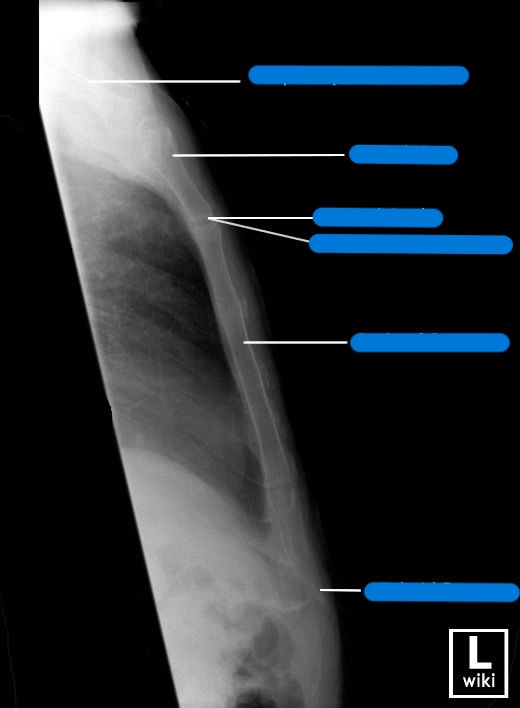

Explain patient and CR positioning for a lateral sternum

patient

erect

lateral position (R or L)

seated or standing

shoulders and arms drawn backward

recumbent

lateral position (R or L)

true lateral

arms raised above head, shoulders back

CR

perpendicular to mid-sternum entering lateral border

top of IR 1½ inches above jugular notch

What are breathing instructions for a lateral sternum? Why?

full inspiration; to get high contrast between posterior surface of sternum and lungs

What is SID for lateral sternum images?

Erect: 72”

Recumbent: 40”

Trauma shoot-thru: 40-72”

What needs to be demonstrated on a lateral sternum image (film eval)?

lateral view of entire sternum

any fractures or inflammatory processes

marker placed anterior for side down (usually L)

collimation anterior to posterior

oriented how you took the image